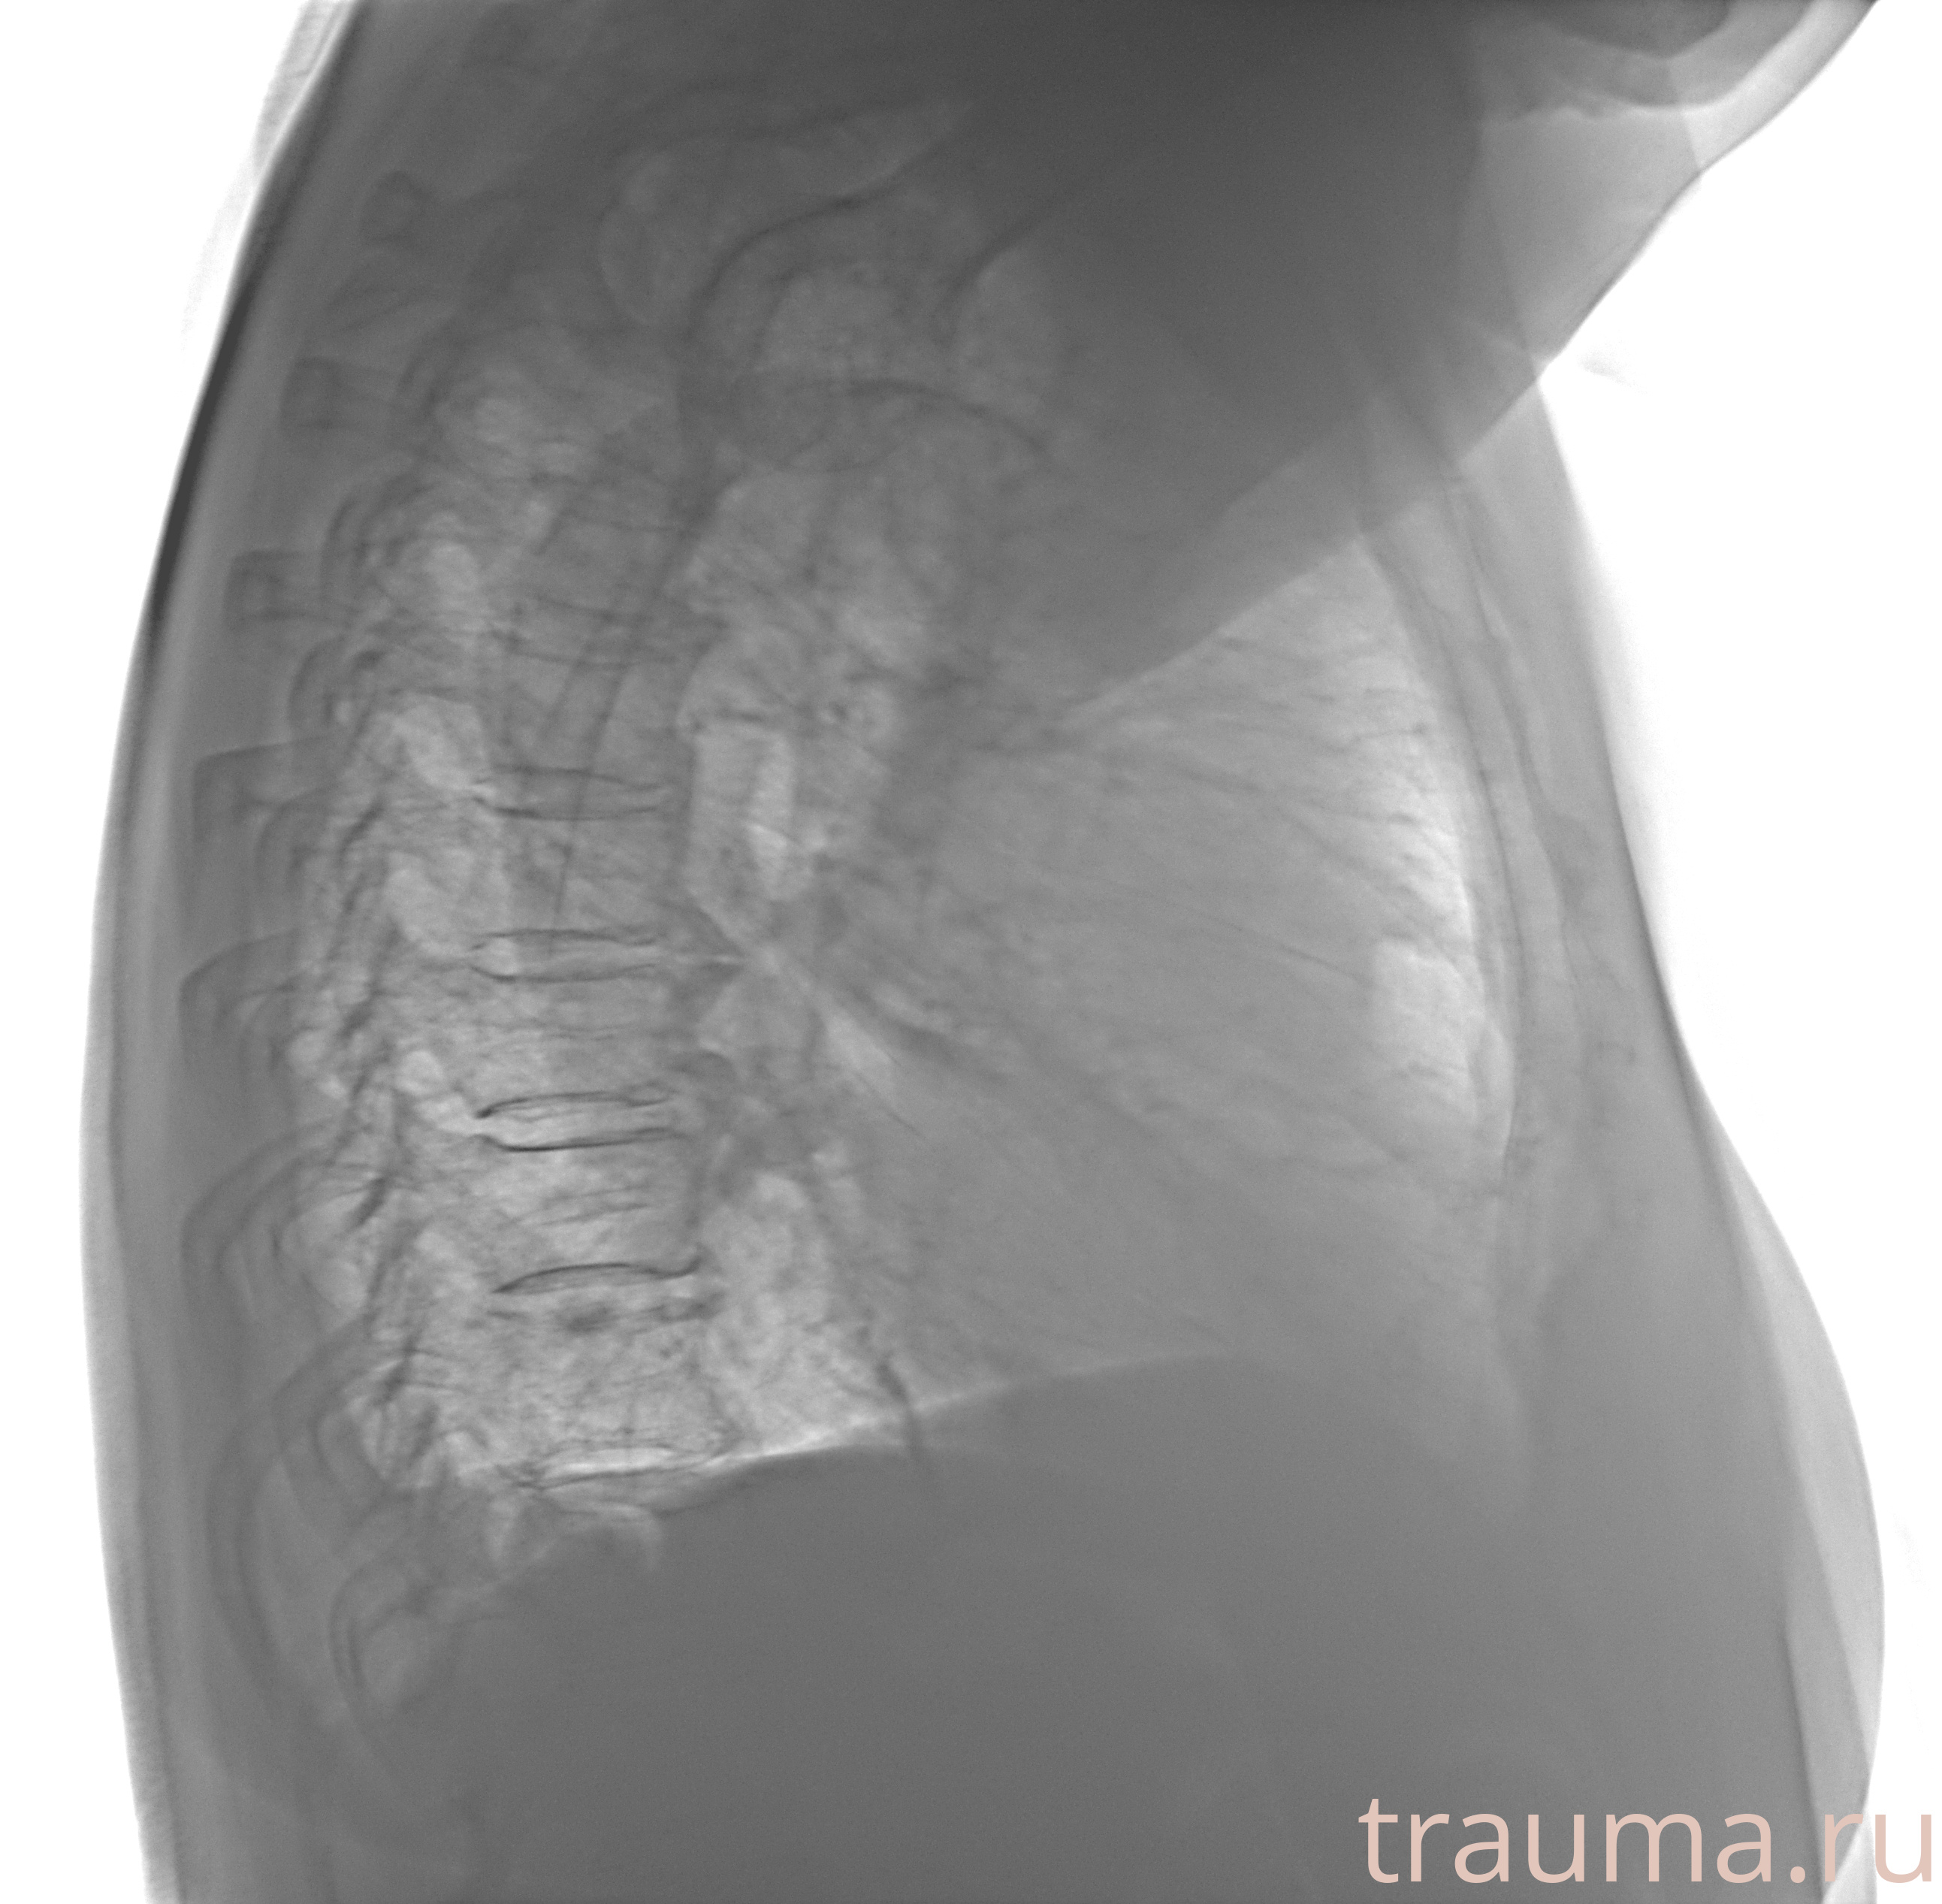

Рентген на дому: по вашему адресу приезжает врач-рентгенолог, травматолог-ортопед с мобильным рентгеновским аппаратом, проводит диагностику травмы или заболевания, делает необходимые рентгенограммы, дает рекомендации по дальнейшему лечению. Получить качественные снимки в домашних условиях возможно благодаря уникальной методике, разработанной МосРентген Центром для института  Склифосовского